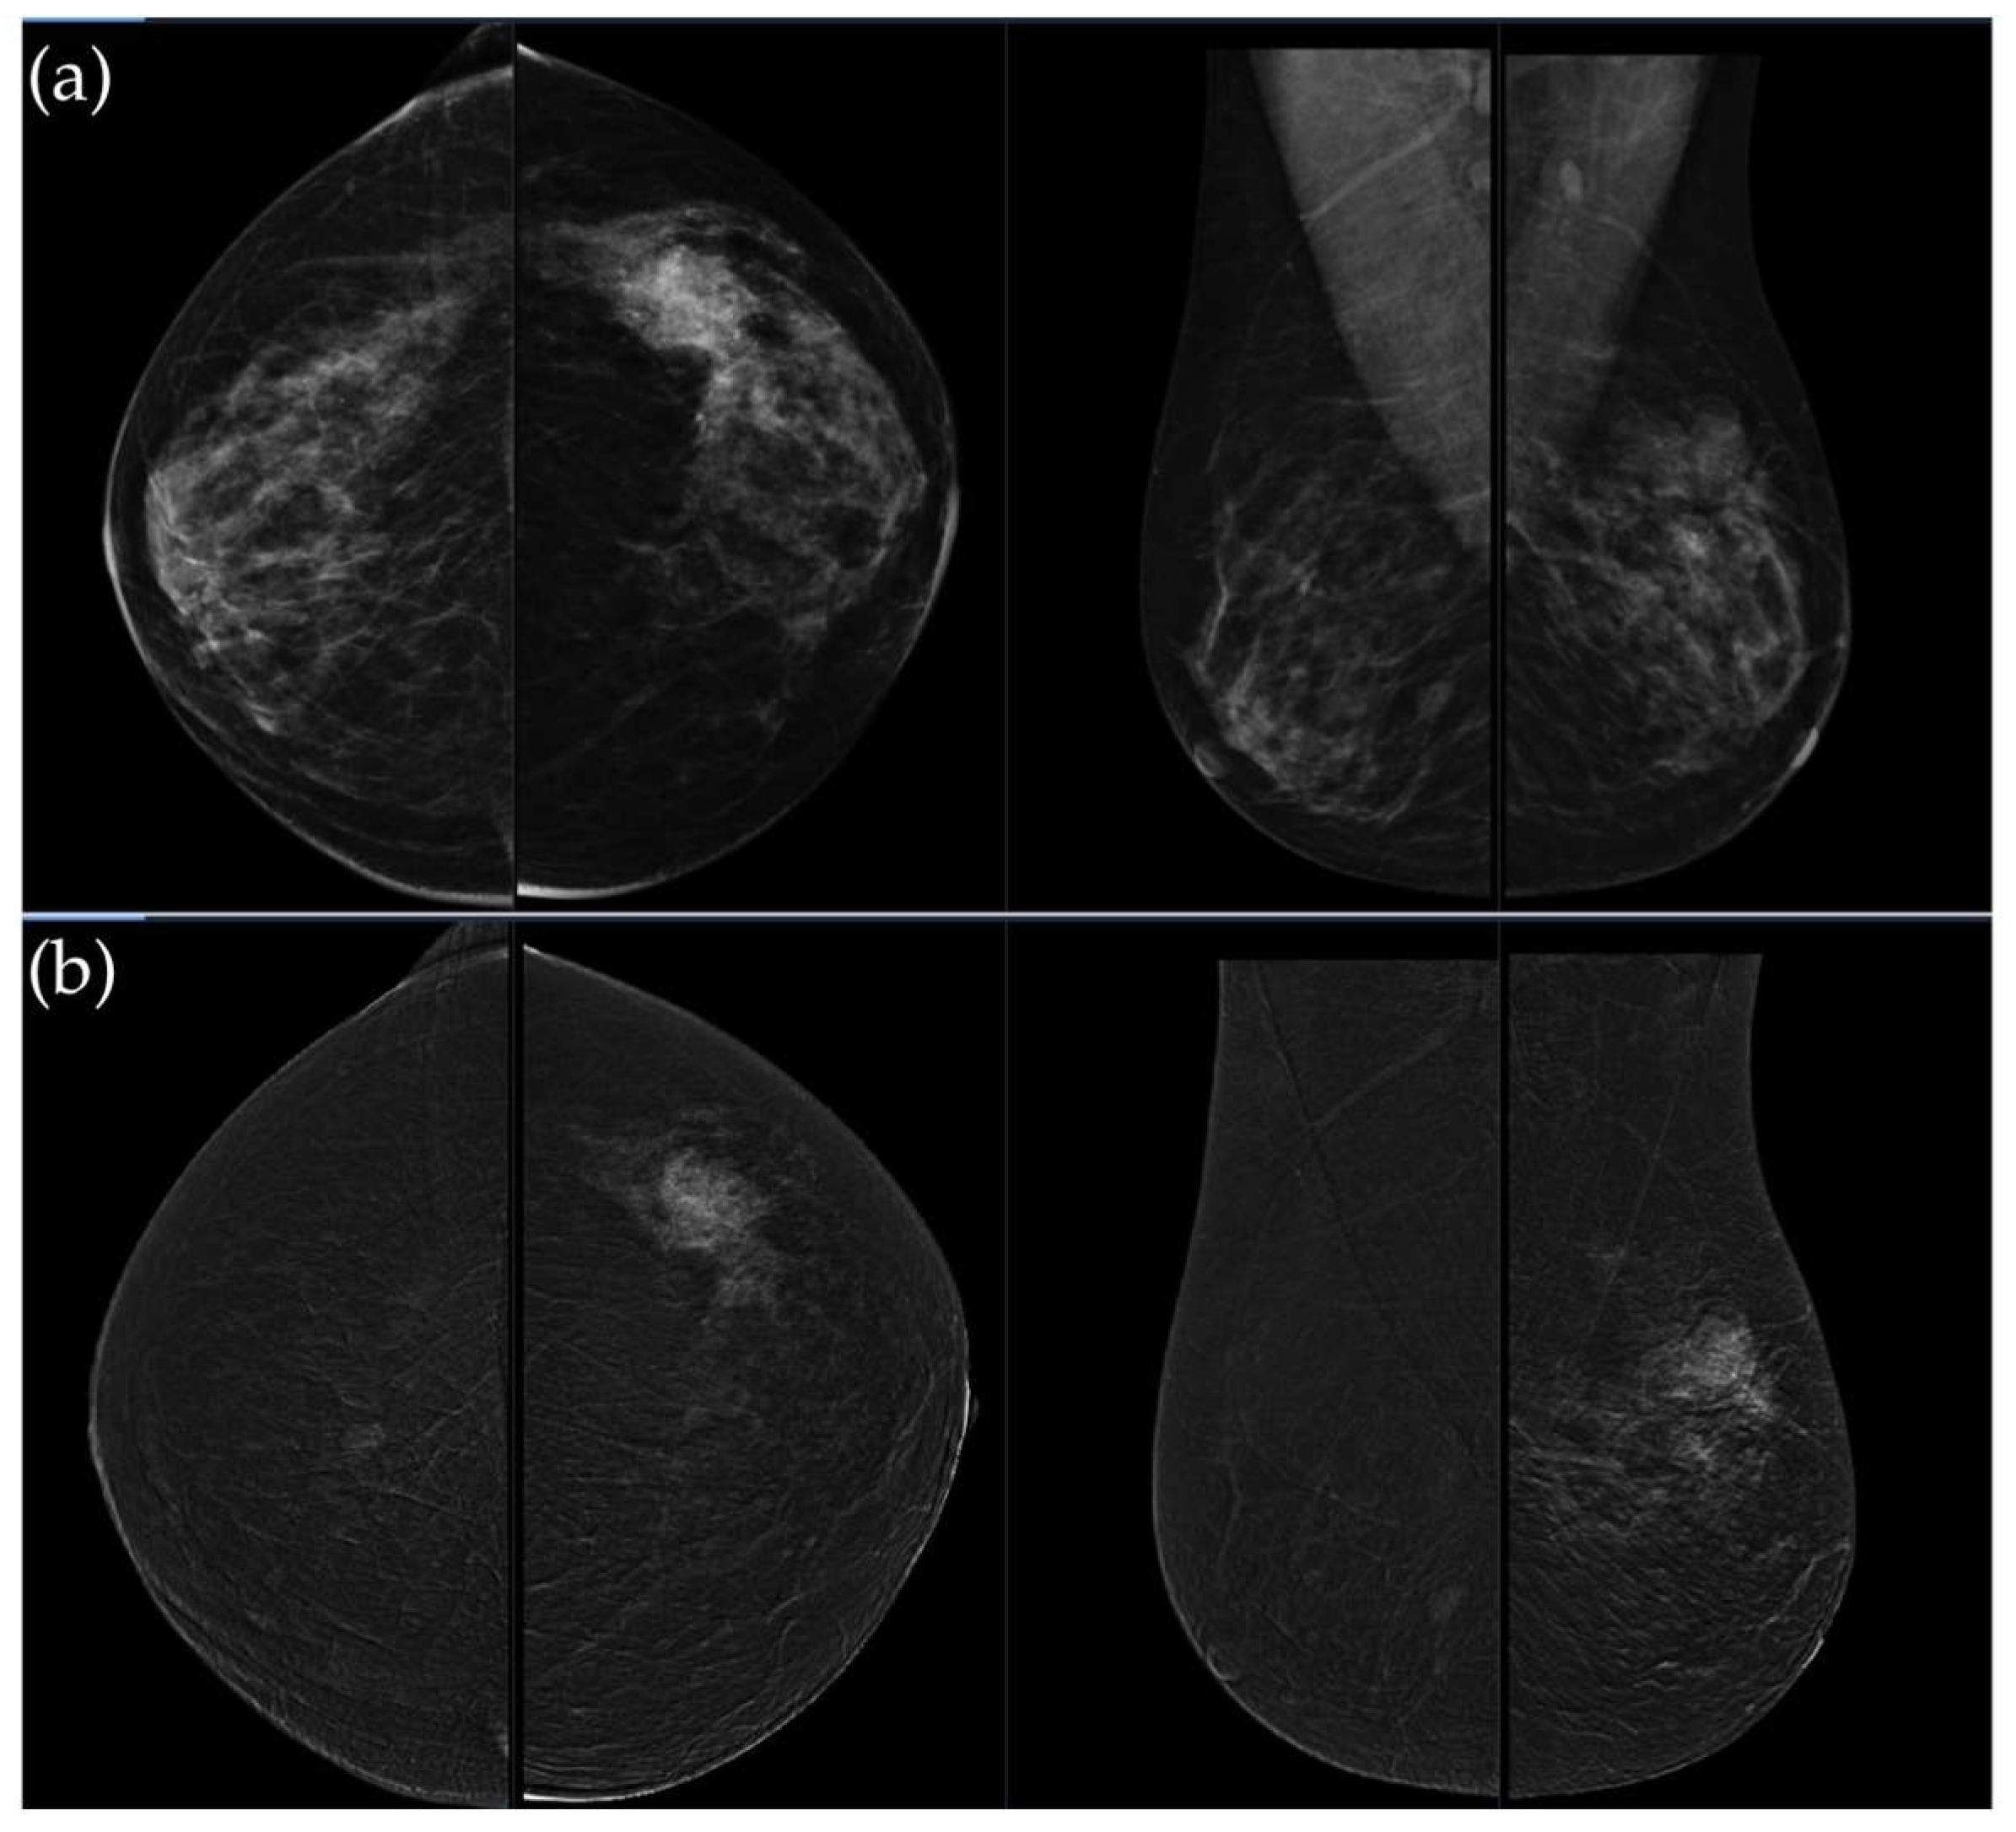

Figure 3. (a) Standard craniocaudal (CC) and mediolateral oblique (MLO) low-energy views reveal an irregular, spiculated mass of the left breast. The right breast shows a histopathologically confirmed fibroadenoma with dystrophic calcifications. (b) Recombined contrast-enhanced images (CC and MLO views) demonstrate early, complete heterogeneous enhancement. No pathologically enhancing axillary lymph nodes are detected. Histopathological analysis confirmed Luminal A breast carcinoma.